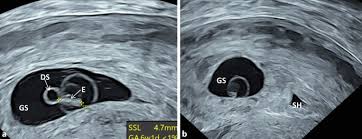

Der Dottersack Ein Wichtiger Marker Beim Ultraschall In Der Fruhschwangerschaft Springerlink